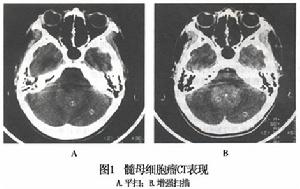

1.頭顱X線平片 頭顱X線可見有顱縫增寬等顱內高壓征,腫瘤鈣化極為罕見。2.CT 可見小腦蚓部或四室內均勻一致的等密度或稍高密度占位,多與四腦室底有分界,將腦幹向前推移。腫瘤周邊環繞有薄的低密度水腫帶明顯均勻強化腫瘤鈣化囊變少見。典型髓母細胞瘤一般直徑大於3.5cm,位於後顱凹中線之小腦蚓部累及上蚓部的腫瘤延伸到小腦幕切跡之上在頭顱CT上87%呈現為均勻一致的高密度影10%為等密度病灶,病灶中有小壞死時平掃亦可呈不均勻之混雜密度少數有鈣化,偶可呈低密度囊性變病灶邊界均較清晰多位於小腦蚓部,成人患者可多見於小腦半球增強檢查呈均勻一致的強化。有時病灶周圍環繞有一條薄的低密度水腫帶第四腦室常被推移向前,可伴有梗阻性腦積水征。當出現腦室室管膜下轉移時,可在腦室周邊出現完全或不完全略高密度影像,成帶狀,可有明顯強化。與室管膜瘤的鑑別主要是髓母細胞瘤的鈣化及囊性變少見,病灶密度比較均勻。3.MRI 腫瘤實質部分表現為長T1長T2信號矢狀位可更好地顯示腫瘤起源於小腦的蚓部及腫瘤與四腦室底的關係見圖2圖3所示,這可視為與室管膜瘤的鑑別點在MRI T1圖像上,腫瘤一般信號強度均勻發生壞死或囊變時,腫瘤內部可見到較腫瘤更長T1、更長T2的病灶區。在T2圖像中67%腫瘤呈高信號,另33%例呈等信號97%瘤周有明顯水腫。由於髓母細胞瘤的實質部分信號強度的特點不甚突出,故腫瘤所在部位及由此而產生的間接徵象則顯得較為重要,可了解與腦幹之間關係,因此正中矢狀掃描圖像尤為關鍵,冠狀掃描可作為三維影像參考在MRI矢狀點陣圖像上74%可見腫瘤與第四腦室底間有一極細長的低信號分隔帶與室管膜瘤不同髓母細胞瘤很少向第四腦室側隱窩及橋小腦角伸展。少數患者MRI可見腫瘤沿蛛網膜下腔轉移,顯示小腦葉的邊界模糊,MRI矢狀位或冠狀位掃描更有價值同時種植病灶亦可被Gd-DTPA顯著增強。97.5%伴有中至重度腦積水。髓母細胞瘤Gd-DTPA增強掃描,腫瘤的實質部分呈顯著異常增強而囊變或壞死區在非延遲掃描狀態下不表現增強。髓母細胞瘤很少有囊性變,腫物位於上蚓部可經小腦幕切跡孔伸入松果體區。